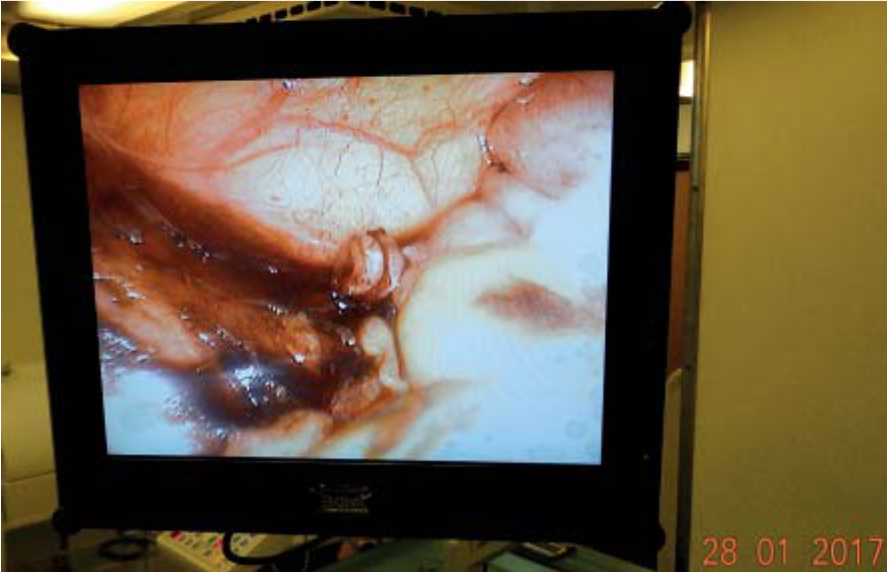

Выполнена диагностическая лапароскопия, в ходе которой выявлен флегмонозно измененный червеобразный отросток, расположенный типично (рис. 2).

Рис. 2. Интраоперационная картина в брюшной полости. Червеобразный отросток с инъецированными сосудами, петехиальными кровоизлияниями, отечен, с наложениями фибрина, расположен типично